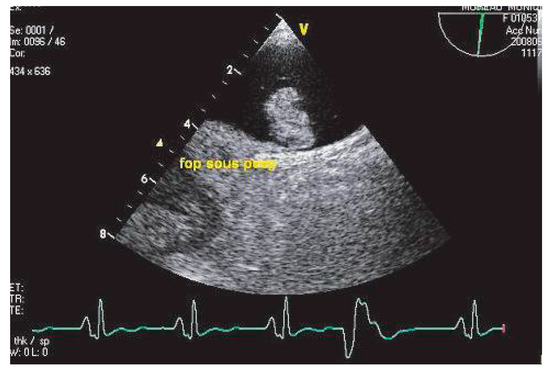

Echocardiographie et Sources Cardiaques d'embolie

• Ariel Cohen

Cardioembolic stroke is the second cause of ischemic stroke, with a high rate of morbidity and mortality. Echocardiography, mainly transesophageal echocardiography, is very useful for the diagnosis and risk stratification of the various potential car...